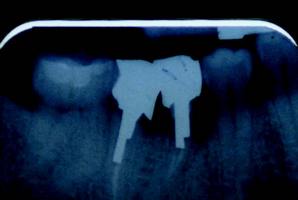

For dentists who are considering becoming involved with placing implants and for novice implantologists, some patients who are already missing teeth present with unpredictable implant sites and more difficult diagnoses (Is the maxillary sinus too close? Is there enough bone to place the implant above the inferior alveolar nerve? What happened to all of the attached gingiva? Is the bone wide enough to accept the implant?). This unpredictability is the main reason general dentists might shy away from learning to place implants and these are the same concerns of most new implantologists as they move ahead in their education.

As the primary dental care provider, the general dentist is perfectly positioned to not only make the diagnosis, but to educate and treat the patient to completion. Once the treatment has been accepted, the hopeless root (with no ferrule) is atraumatically extracted. If both the buccal and lingual walls remain intact, simple socket preservation techniques can be utilized so that in three to four months the general dentist now has “created” an optimal implant site. If pathology or less than traumatic extraction leaves you with a compromised buccal or lingual boney plate, then socket augmentation is performed, and an optimal implant site is available for implant placement in four to five months.